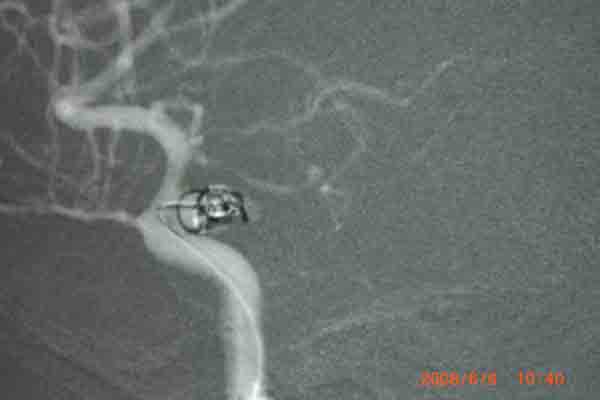

6月6日上午,在明州医院放射科的DSA检查室内。上海的神经外科专家及麻醉科在为一位38岁的云南来宁波打工中年女病人做颅内动脉瘤(眼颈交界处7*3.5cm)血管内栓塞手术。无影灯下,准备工作在有条不紊地进行着。全身麻醉后。介入手术开始了,手术医生以非常娴熟的手法,在右侧股动脉内置入导管,在显像下,随着导丝进入,顺利到达动脉瘤瘤腔内。随着弹簧圈进入,瘤腔内被充填。造影后,显示位置良好。所有的神经外科医生知道,在手术过程中,如果发生动脉瘤破裂,那后果不堪设想。手术成功了,大家悬着的心放下了。整个手术时间仅仅用了1个半小时。手术后,病人即清醒,送回病房。

回想这个病人是5月 20 日,因为在早晨起床后,突然昏迷不醒,跌到在地,被家人送往明州医院急症室,经过医生检查,这个病人已经瞳孔放大,呼吸停止。紧急地插入气管导管后,给予呼吸机使用。经过医院上海神经外科专家检查病人后,指出这是动脉瘤破裂出血导致的呼吸压制。需要头颅CT检查,在捏着皮球保持呼吸道通畅,即刻行头颅CT检查,确认为动脉瘤破裂出血,前交通动脉瘤破裂为主。专家看了片子后,认为如果行双侧脑室外引流,将血液引出,可能会使呼吸恢复。马上送手术室做急症手术,引流出血性脑脊液后,病人呼吸慢慢恢复了。经过3个星期的正规治疗(高血压,高颅压,高体温)(抗血管痉挛,抗感染)(外引流)病人终于度过了危险期。在6月6日上午成功进行了颅内动脉瘤血管内栓塞手术。